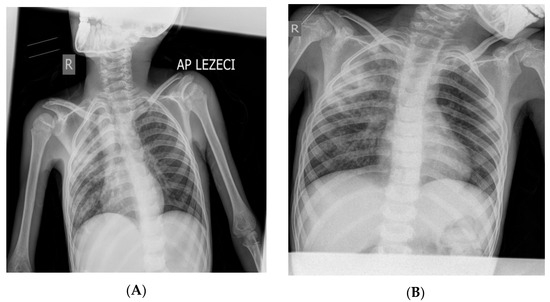

The Difficulty Detecting Tuberculosis in a Child with Post-COVID-19 and Cerebral Palsy